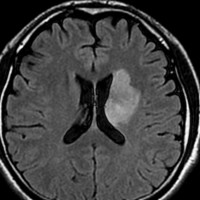

4回目のアバスチン投与後

アバスチンをどれだけ続ければいいのかははっきりしていません。2週間おきに6コースまでの投与が基本かもしれません。

この画像を見ると,放射線とテモダールの治療が有効であったのかなと思います。